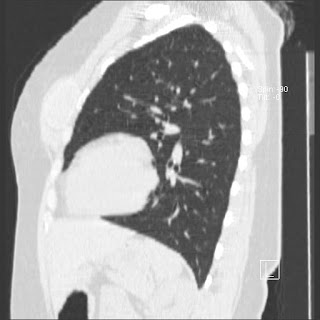

New CT images (without contrast) for 40 year old female with silicone breast implants. Formal diagnosis is expected soon. Images from 2010 can be seen here http://radiology-images.blogspot.com/p/40-year-old-female-silicone-implants.html